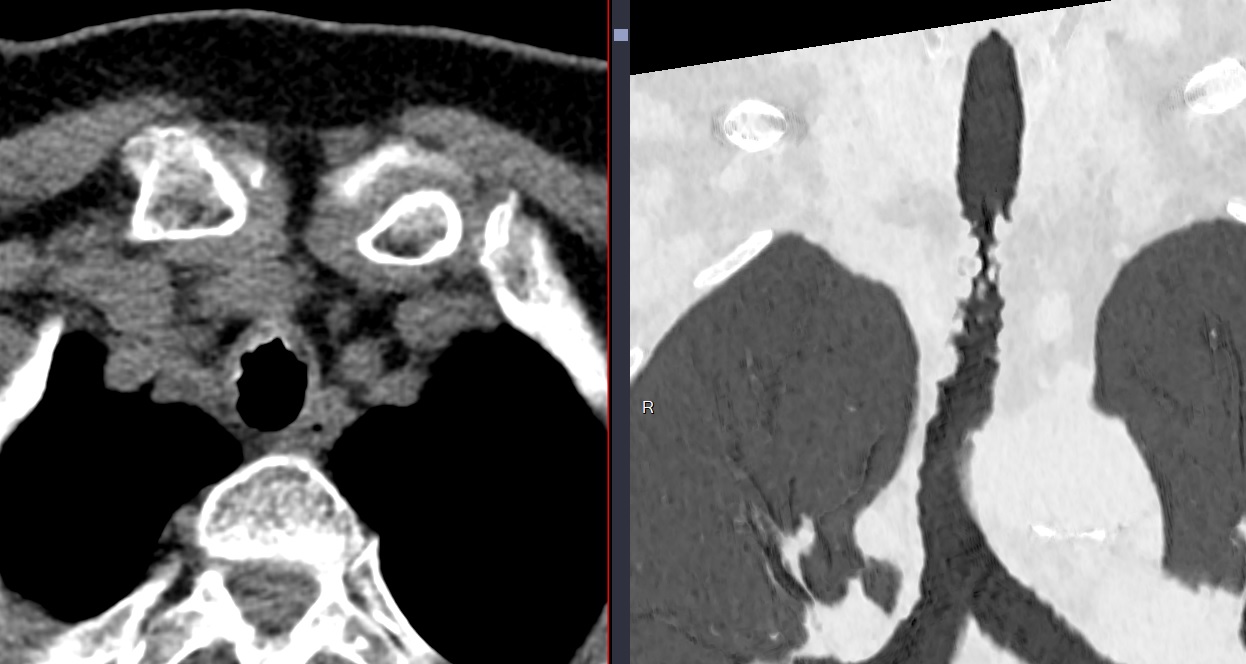

Cas

Tracheobronchopathia Osteochondroplastica